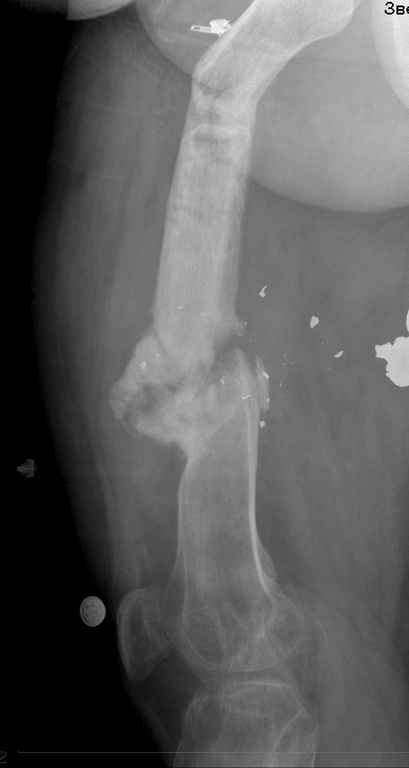

[Ortho] ложный сустав бедра

посылаю снимки отдельно

Имя     : 1.jpg